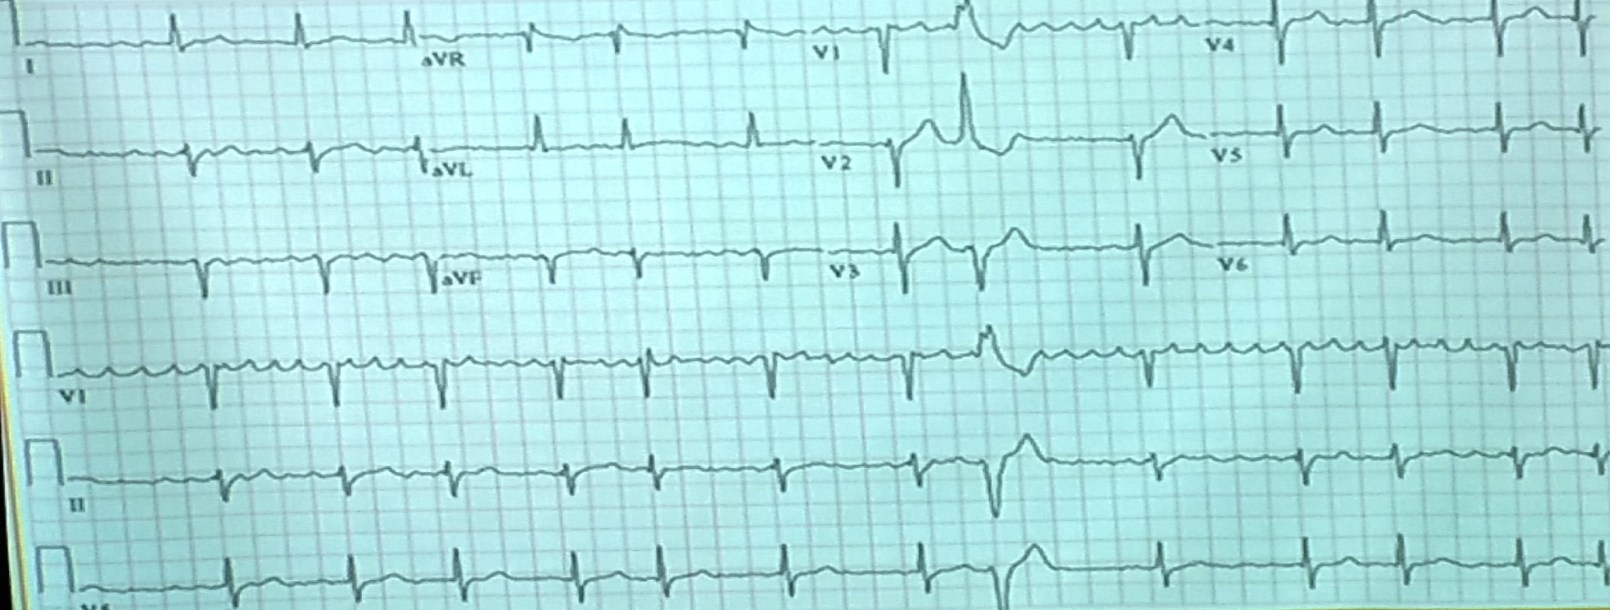

Case 5 Z

- Describe 2 abnormal features of the ECG?

a. ST elevation

b. Increase PR interval

PR segment depression and ST segment elevation in the inferior leads (II, III, aVF) and precordial leads (V2 V6), most prominent in leads V2 and V3, with reciprocal ST depression in aVL. There are also widespread T wave inversions.

Likely diagnosis is acute pericarditis.

- What is the ECG diagnosis?

a. Pericarditis